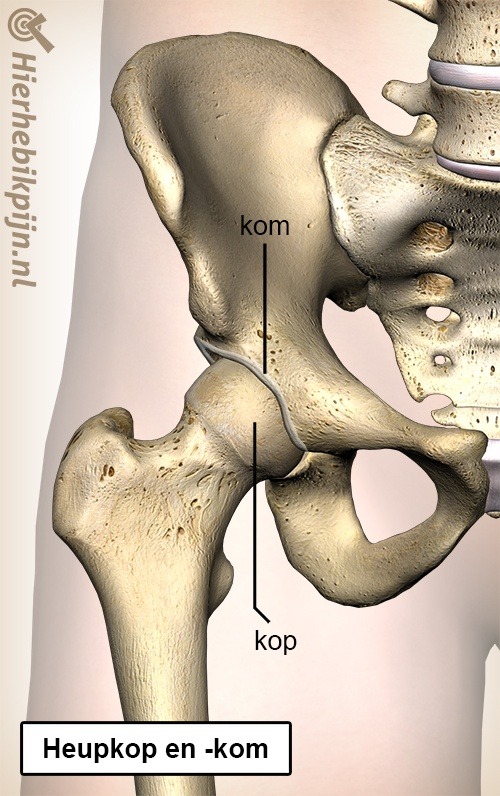

page_id_141_lead

page_id_141_body